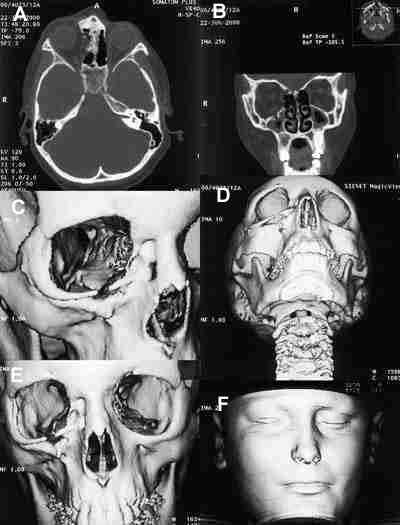

Diagnóstico diferencial de los tumores vasculares orbitarios

Los tumores vasculares orbitarios más frecuentes en la infancia, ya hemos dicho que son el hemangioma capilar (figura 9) y el linfangioma (figuras 10 y 11), pero también, aunque son más raros, se pueden ver los hemangio-pericitomas y los hemangiomas cavernosos. La varíz orbitaria, es una malformación venosa generalmente congénita que se manifiesta con frecuencia en las primeras décadas de la vida y es la principal causa de hemorragias orbitarias. Hay otras entidades mucho menos frecuentes en la infancia como la malformación arteriovenosa y la fístula carótido-cavernosa que producen aumento de tamaño de las venas orbitarias (17).

53-09.jpg (12346 bytes)

Figuras 9a, b, c y d. Hemangioma capilar. TC axial con adquisición helicoidal (a) con reconstrucción sagital (b). RM en secuencias sagital T1 y coronal T2 (c, d). Masa intra-extraconal hipercaptante con imágenes de vacío correspondientes a pequeños vasos en la RM (a).

53-10.jpg (19860 bytes)

Figuras 10a, b, c, d, e y f. Típica localización de linfangioma orbitario en la región cantomeatal. Secuencias potenciada en T1 con gadolínio (a) y en T2 (b) en las que no se observa afectación retrobulbar. TC axial en ventana ósea (c) y parenquimatosa (d) con reconstrucción tridimensional ósea (e) y de piel (f) muestran asimetría de párpado inferior y ausencia de afectación ósea.

53-11.jpg (13996 bytes)

Figuras 11a y b. Linfangioma: Secuencias coronal (a) y axial (b) potenciadas en T2 que muestran la lesión interconal multilobulada que brilla en T1 y T2.

La localización más frecuente de los procesos vasculares orbitarios es extraconal, excepto el hemangioma cavernoso, que es intraconal, y los linfangiomas y las varices (figura 12) que son mixtas, de situación intra y extraconal. El hemangioma capilar puede extenderse al interior del cráneo a través de la fisura orbitaria inferior, el canal óptico, o el techo de la órbita. (6).

53-12.jpg (15560 bytes)

Figuras 12a, b, c, d, e y f. Variz de la vena oftálmica superior. Secuencia axial potenciada en T1 pre y post administración de gadolínio (a, b). Corte axial con contraste yodado a nivel de la lesión (c) con reconstrucciones biplanares coronales (d) y sagitales (e). Angiografía venosa de la lesión (f). Se observa lesión en región teórica de la vena oftálmica superior que capta contraste marcadamente, y en la angiografía venosa (f) se observa el teñido correspondiente a la variz.